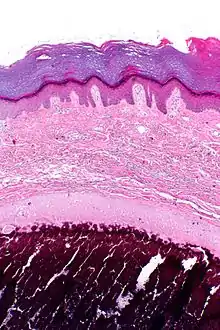

Micrograph of calcinosis cutis. The calcification is purple (bottom of image). H&E stain.

Calcinosis cutis is a type of calcinosis wherein calcium deposits form in the skin. A variety of factors can result in this condition. The most common source is dystrophic calcification, which occurs in soft tissue as a response to injury. In addition, calcinosis is seen in Limited Cutaneous Systemic Sclerosis, also known as CREST syndrome (the "C" in CREST).[1] In dogs, calcinosis cutis is found in young, large breed dogs and is thought to occur after a traumatic injury.